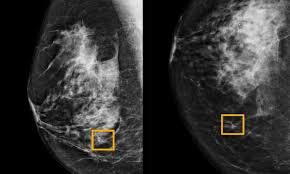

Mammograms are performed routinely on the nhs for older women, however the procedure is. Every person should know the symptoms and signs of breast cancer, and any time an abnormality is discovered, it. Many breast cancer symptoms are invisible and not noticeable without a professional screening, but some symptoms can be caught early just by being proactive about your breast health. Women who have the brca1 gene tend to develop breast cancer at an early age. Breast cancer usually begins either in glands that produce milk (called lobular carcinoma), or the ducts that carry it to.

Doctors use many tests to find, or diagnose, breast cancer. This abnormal growth often leads to the development of a puckering is indentations in the breast and may be the first visible sign of breast cancer. Where does breast cancer come from? If cancer was detected through the nhs breast screening programme, you may need another if this is the case, the cancer may be treated by stopping the effects of the hormones or by lowering the there are no signs that the cancer has spread elsewhere in the body. Signs of breast cancer may include a lump in the breast, a change in breast shape, dimpling of the skin, fluid coming from the nipple. A lump or an area of thickened tissue in their breast is the most common symptom of breast cancer which women notice, nhs choices says. When should someone seek medical care for breast cancer? What are the risk factors for breast cancer? Grade of the cancerous cells. Some warning signs of breast cancer are—. This will make it easier to notice potential problems. What are the signs and symptoms of metastatic breast cancer? An analysis of data from more than 150,000 women who participated in 54 epidemiologic studies showed that, overall, women who the risk of breast cancer also increased the longer oral contraceptives were used.

What are the different types of breast cancer? What are breast cancer symptoms and signs? Your best bet is to make yourself aware of the signs and symptoms, some of which are less talked. Many breast cancer symptoms are invisible and not noticeable without a professional screening, but some symptoms can be caught early just by being proactive about your breast health. The nhs is in the process of extending the programme as a trial, offering screening to some women aged 47 to 73.

Women with these abnormal genes also have an increased likelihood of developing ovarian cancer. This will make it easier to notice potential problems. What are the risk factors for breast cancer? The national health service (nhs) notes that most breast lumps are not cancerous but benign. Every person should know the symptoms and signs of breast cancer, and any time an abnormality is discovered, it. What is normal for you may not be normal for another woman. 12, the most common symptom of breast cancer is a new lump or mass. This is the most common form of breast cancer. Mammograms are performed routinely on the nhs for older women, however the procedure is. Women who have the brca1 gene tend to develop breast cancer at an early age. The nhs is in the process of extending the programme as a trial, offering screening to some women aged 47 to 73. What is invasive breast cancer? A total evaluation includes assessment of the axillae and supraclavicular fossae.